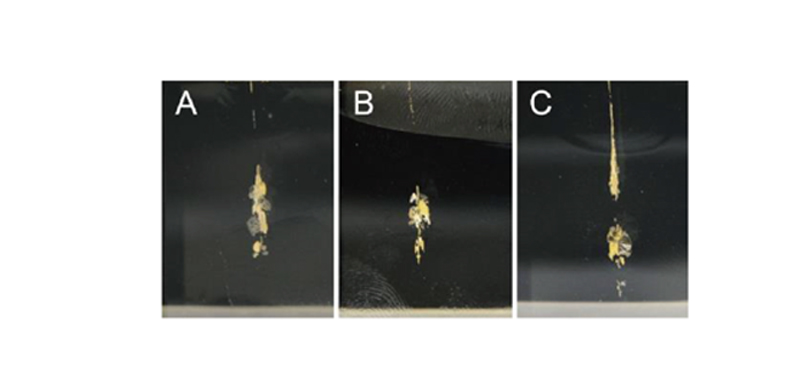

Transcutaneous Pneumatic InjectionSHEMAX uses compressed air pressure to spray liquid medicine instantaneously.

At this time, liquid medicine is delivered to a certain depth through physical energy.